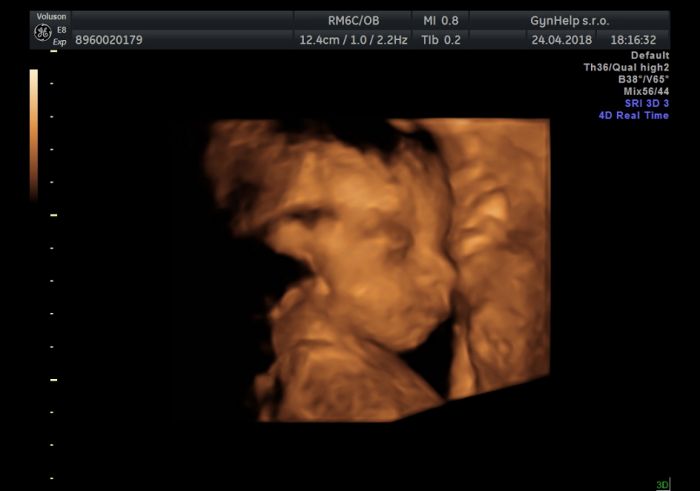

Jinak jsme byli na 4D a bylo to fajn, akorát Jonáš moc nespolupracoval :D, ale tak nějak se ve finale zadařilo.